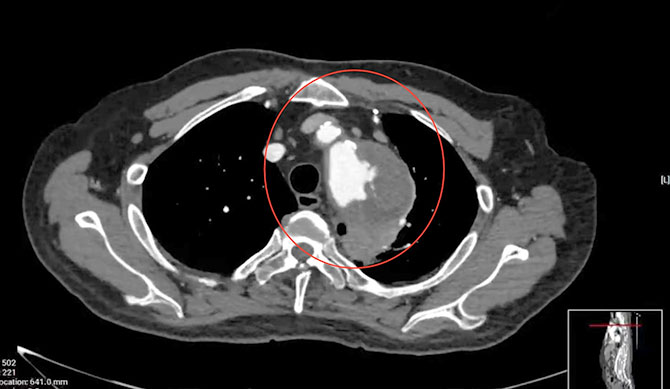

68岁的钟先生(化名),在一年前发现主动脉弓部动脉瘤,未予重视,直到数月前因瘤体增大压迫左侧喉返神经出现声嘶,半月前咳血丝痰,在外院行CTA检查提示主动脉弓动脉宽约60mm,才前往我院血管外科王劲松主任门诊就诊,拟“胸主动脉瘤,主动脉弓动脉瘤”收治入院。钟先生的瘤体巨大,濒临破裂,一旦破裂出血容易造成出血性休克,将会有生命危险。钟先生合并有高血压病史、冠心病史、糖尿病史,2011年曾行冠脉搭桥手术。心功能不佳,加上主动脉弓病变累及分支动脉(无名动脉、左颈总动脉、左锁骨下动脉),病变复杂,治疗难度较大。钟先生入院后,王劲松主任、张朝晖医生、赵成磊医生组成医疗团队,立即为钟先生完善相关检查,予降压、降脂等对症处理,避免瘤体进一步扩大,降低出血风险。同时,联合体外循环周成斌主任医师、心外科李欣主任医师、麻醉科于冬男主任医师、放射科刘辉主任医师等进行多学科诊疗,制定微创主动脉腔内修复治疗方案。

患者主动脉弓动脉瘤体巨大,濒临破裂